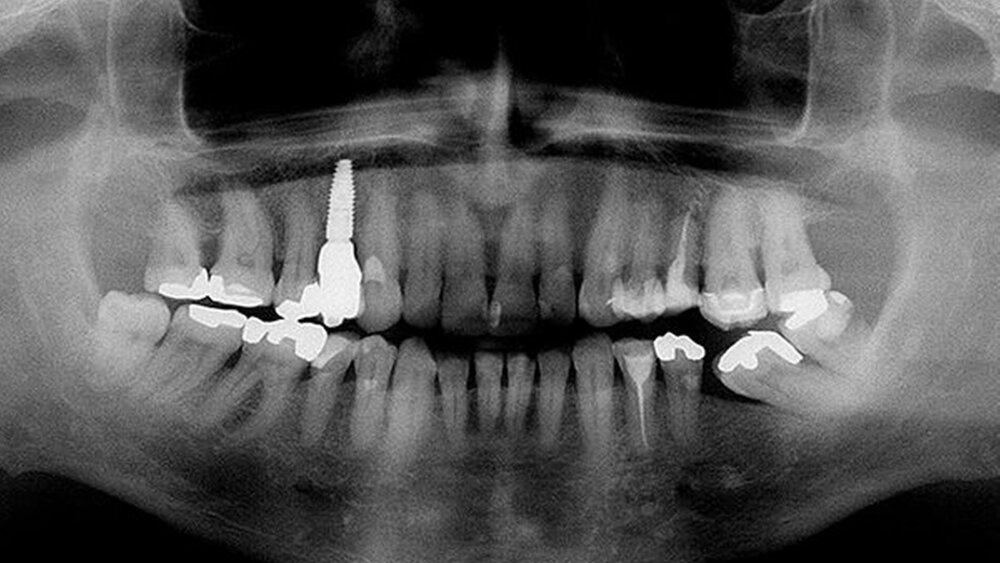

Der folgende klinische Fall dokumentiert die Behandlung eines 61 Jahre alten Patienten, der sich initial mit erheblichen Beschwerden an Zahn 14 vorgestellt hatte. Die radiologische Untersuchung (Abb. 1) ergab eine periapikale Aufhellung sowie eine insuffiziente Wurzelkanalbehandlung. Im Folgenden wurde die Krone entfernt und eine Revision der Wurzelkanalbehandlung durchgeführt. Im Rahmen der Revisionsbehandlung stellte sich eine Längsfraktur im Bereich der vestibulären Wurzel dar. Aufgrund der daraus resultierenden schlechten Prognose einer weitführenden konservierenden Therapie wurde der Zahn atraumatisch entfernt und die Alveole sorgfältig von Granula‧tionsgewebe und einem sich apikal befindenden Zystenbalg befreit (Abb. 2). Das gewonnene Gewebe wurde der histopathologischen Untersuchung zugeführt; dabei ergab sich das Bild einer radikulären Zyste. Aufgrund der latent vorhandenen Inflammation im Bereich der Alveole wurde auf eine sofortige Augmentation mit Knochenersatzmaterial im Sinne einer Ridge Preservation verzichtet. Die Alveole wurde konventionell mit einem Kollagenkegel und einer adaptierenden Naht versorgt. Nach Besprechung mit dem Patienten wurde eine implantatprothetische Versorgung geplant. In der ersten chirurgischen Phase (sechs Wochen nach der Extraktion) erfolgte ein horizontaler Alveolarkammaufbau mittels GBR-Technik unter Lokalanästhesie, um das abgebaute Knochengewebe wiederherzustellen und damit ein entsprechendes Implantatbett zu gestalten. Präoperativ zeigten sich vestibulär in regio 14 sowohl der Knochen als auch das Weichgewebe defizitär (Abb. 3). Im Rahmen der geplanten Augmentation erfolgte die Bildung eines lokalen Mukoperiostlappens in regio 14. Aufgrund der aus den vorhergegangenen operativen Eingriffen resultierenden Narbenzüge im OP-Gebiet wurde auf eine gängige Lappenextension über das Augmentationsgebiet hinaus verzichtet. Nach Lappenbildung konnte der wandige Defekt exploriert und intensiv mit physiologischer Kochsalzlösung gespült werden (Abb. 4). Im Anschluss erfolgten die Vorlage einer neuen nicht resorbierbaren Membran (permamem, botiss biomaterials, Zossen, Deutschland) sowie der Zuschnitt der Membran entsprechend der Größe des abzudeckenden Defekts (Abb. 5). Es folgte die Augmentation des wandigen Knochendefekts mit allogenem Knochenersatzmate‧rial (maxgraft spongiöse Granula, botiss biomaterials), das zuvor mit venösem Eigenblut des Patienten durchmischt worden war (Abb. 6 und 7). Danach wurde das Augmentat mit der vorgelegten nicht resorbierbaren Membran abgedeckt (Abb. 8). Der Wundverschluss erfolgte mittels horizontaler Matratzennaht und Einzelknopfnähten (Resolon 4.0/5.0, Resorba, Nürnberg, Deutschland) (Abb. 9). Die postoperativ angefertigte Halbseiten-Panoramaschichtaufnahme zeigte eine vollständige Augmentation der Defektregion (Abb. 10).